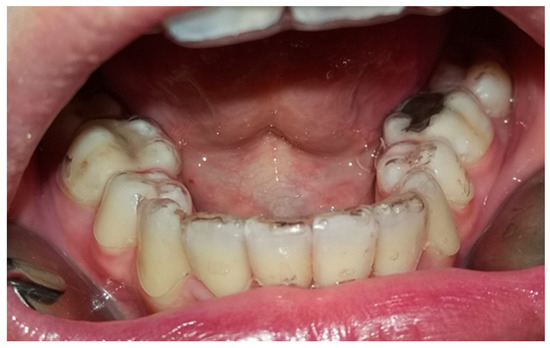

The Hawley retainer designed by Charles Hawley in 1920 (Figure 1) has proven its effectiveness for more than a century. Along with the retention, it can also be an active orthodontic instrument which, through the action of mechanical forces, produces small changes such as the closure of the remaining interdental spaces due to the anchoring by the orthodontic rings [18].

Figure 1. Hawley retainer used in the study.